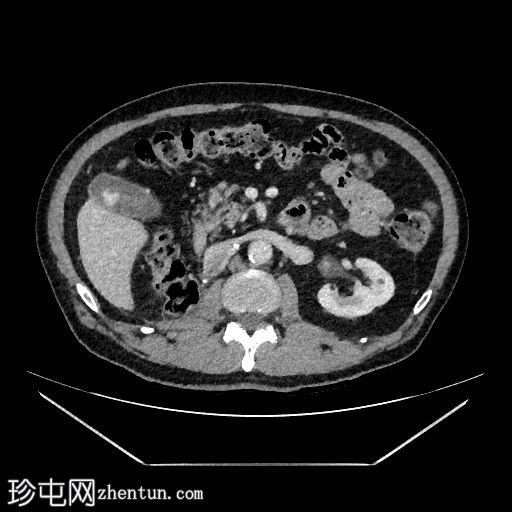

轴位T1加权像

4.jpg

同相位

5.jpg

反相位

增强扫描(C+)脂肪抑制

行MRI检查以明确病因。 MRI显示胆囊底部有一孤立性息肉样病变,突入胆囊内,大小约为21 mm x 17 mm。病变表面可见高T1信号,可能代表血液成分。病变早期增强扫描后强化程度较正常胆囊壁更为明显。